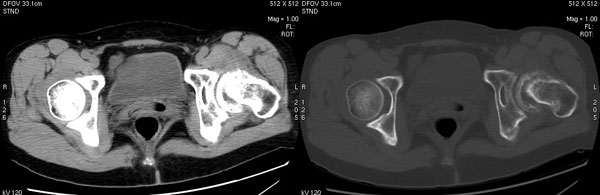

以下是引用jiajie在2006-7-14 17:19:00的发言:[br]ct所见:双侧髋关节不对称,左侧关节间隙变窄,关节面毛糙。左侧股骨头变形、无明显变小,前上缘与髋臼融合,融合处骨质明显增生硬化,并见数个小囊变影。股骨头下端与股骨颈交界部见囊样变,邻近肌肉内见囊样密度减低区,ct值24hu。右侧髋关节形态未见异常。[br][br]ct诊断:左侧髋关节结核可能,请结合临床资料进一步分析。

以下是引用lihuuuu在2006-12-5 10:14:00的发言:[br]定位像示:左侧髋臼变浅,倾斜度加大,髋臼外上缘呈波浪状不规则,骨质增生硬化,髋关节上缘间隙明显变窄,股骨头向外上轻度移位。轴位像示:左侧股骨头变形,前上缘与髋臼融合,融合处骨质明显增生硬化,并见数个小囊变影。股骨头下端与股骨颈交界部见囊样变,邻近肌肉内见密度减低区,ct值24hu,内缘见弧形高密度钙化影。右侧髋关节形态未见异常。[br]ct诊断:左侧髋臼发育不良[br] 左侧股骨头缺血性坏死[br] 左侧肌肉内低密度影伴有高密度钙化-考虑早期骨化性肌炎[br] [br]“我认为在描述上已经写了肌肉部分,印象诊断里应该写主见”[br]